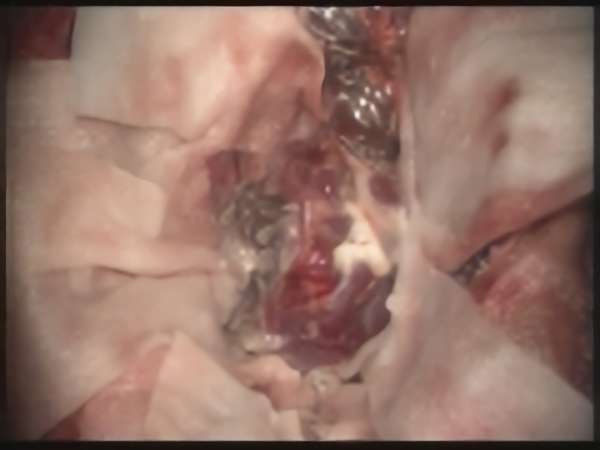

'19年5月

右中小脳脚 出血再発

SM 3(S1,E1,V1)

米国の病院

No.359 モニタリング

No.359 手術前

No.359 手術中

No.359 手術後

出血既往があり。2回の手術前血管内手術の後に、

Lateral transpeduncular approachにより再々出血予防を目的に

摘出手術を行う。完全摘出であることを確認した。

手術による合併症や後遺症なしで退院した。経過良好。